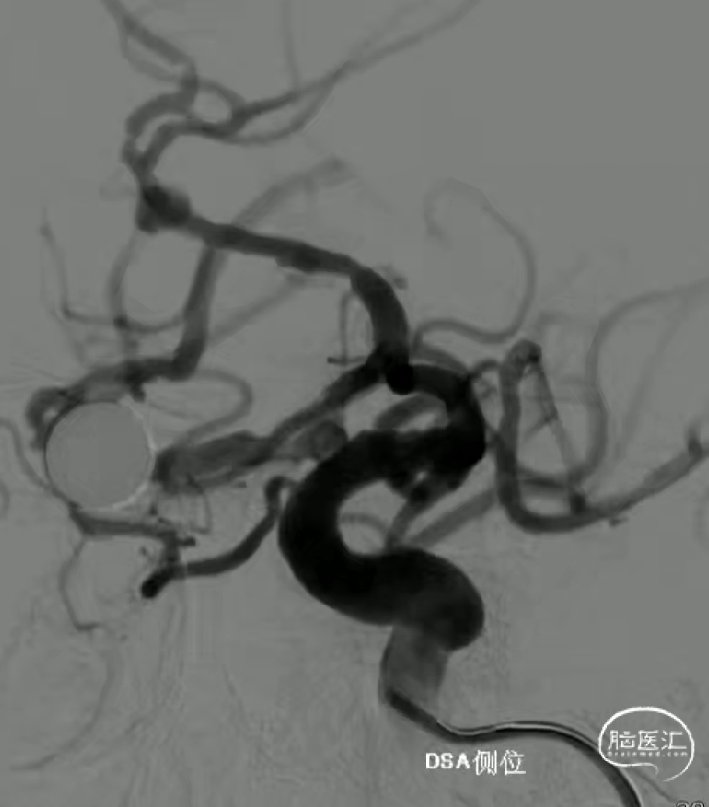

术前影像

· 患者三型弓,奇大脑前A3段动脉瘤,形态极不规则,血管入路极其迂曲

· 从大脑前动脉瘤起始段,有广泛伴有动脉粥样硬化的斑块

· 病变远端处于奇大脑前动脉双分叉位置,远端支架可着陆的空间较短,远端血管较细,且伴随斑块

动脉瘤近端锐角弯曲,颅内支撑导管位置较低,且血管迂曲,无法提供很好的支撑和力的传导,故支架推送中阻力较大,需双手操作,给予支架推送杆一定张力。

中段释放后,造影,动脉瘤滞留明显,支架贴壁打开良好,支架位置合适。

术后即刻造影,动脉瘤滞留明显,载瘤动脉管腔通畅无狭窄,支架贴壁理想。

本例病例奇大脑前A3段动脉瘤,从大脑前动脉瘤起始段有广泛伴有动脉粥样硬化的斑块,血管路径过于迂曲,且颅内支撑导管的位置过低,仅位于C4段,无法提供很好的支撑性和力的传导功能,这样的情况会导致支架推送性能会有下降,释放中会降低可控性,对于这样的病例,颅内支撑导管上到更高,上至颈内动脉瘤末端或A1段会起到更好的帮助。